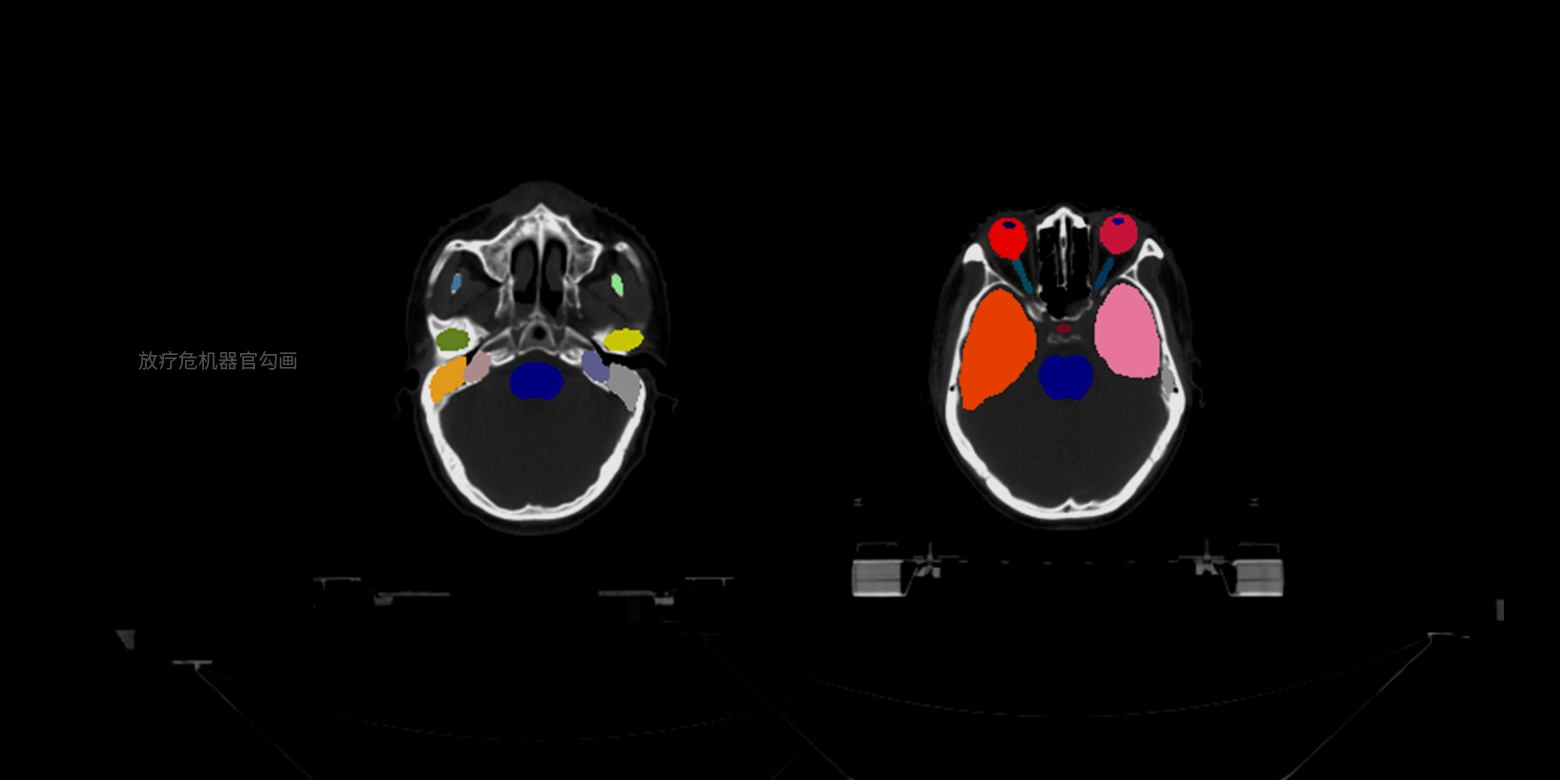

支持基于小样本精细医学数据标注进行训练,实现多种病灶、器官等的像素级精确边界分割,并自动进行关键信息的量化分析,例如放疗靶区勾画、骨盆肿瘤分割等,将医生从耗时耗力的人工手动勾画中解放,满足量化诊断、手术个性化规划等场景的需求。